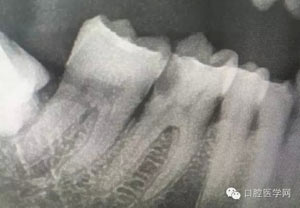

病例1:患者迫切希望保留自己的這一顆牙齒,根尖周陰影比較大,二度松動.而且旁邊有種植修復(fù)體,和患者溝通好后,治療好后觀察一個月后冠修復(fù),因為有種植的后期修復(fù),所以有了機會觀察,術(shù)后三個月和術(shù)后四個月,根尖恢復(fù)的還算不錯,希望能夠繼續(xù)觀察下去.這樣子的病例,做的時候我們一定要非常的小心,和患者要有充分的溝通以及不同科室的溝通然后決定怎么樣做比較好,假如就是出現(xiàn)了問題,到時候我們也比較好處理些,免得我們自己到時候不好收場。